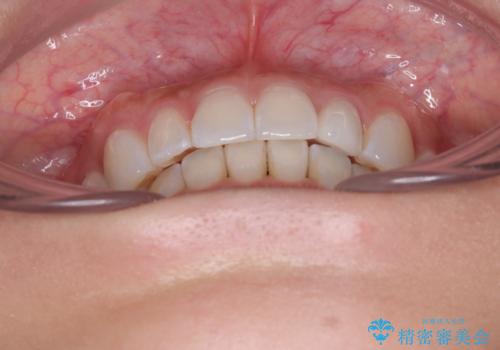

【モニター】前歯のデコボコと小さい前歯 インビザライン矯正とオールセラミッククラウン補綴治療

上下前歯の歯列不正はインビザラインにより整え、その後に、矮小歯の前歯をオーダーメイドタイプのオールセラミッククラウンにて補綴治療することとしました。

セラミッククラウンにて大きさを変更することを前提に矯正治療を開始したため、大変満足のいく仕上がりとなりました。